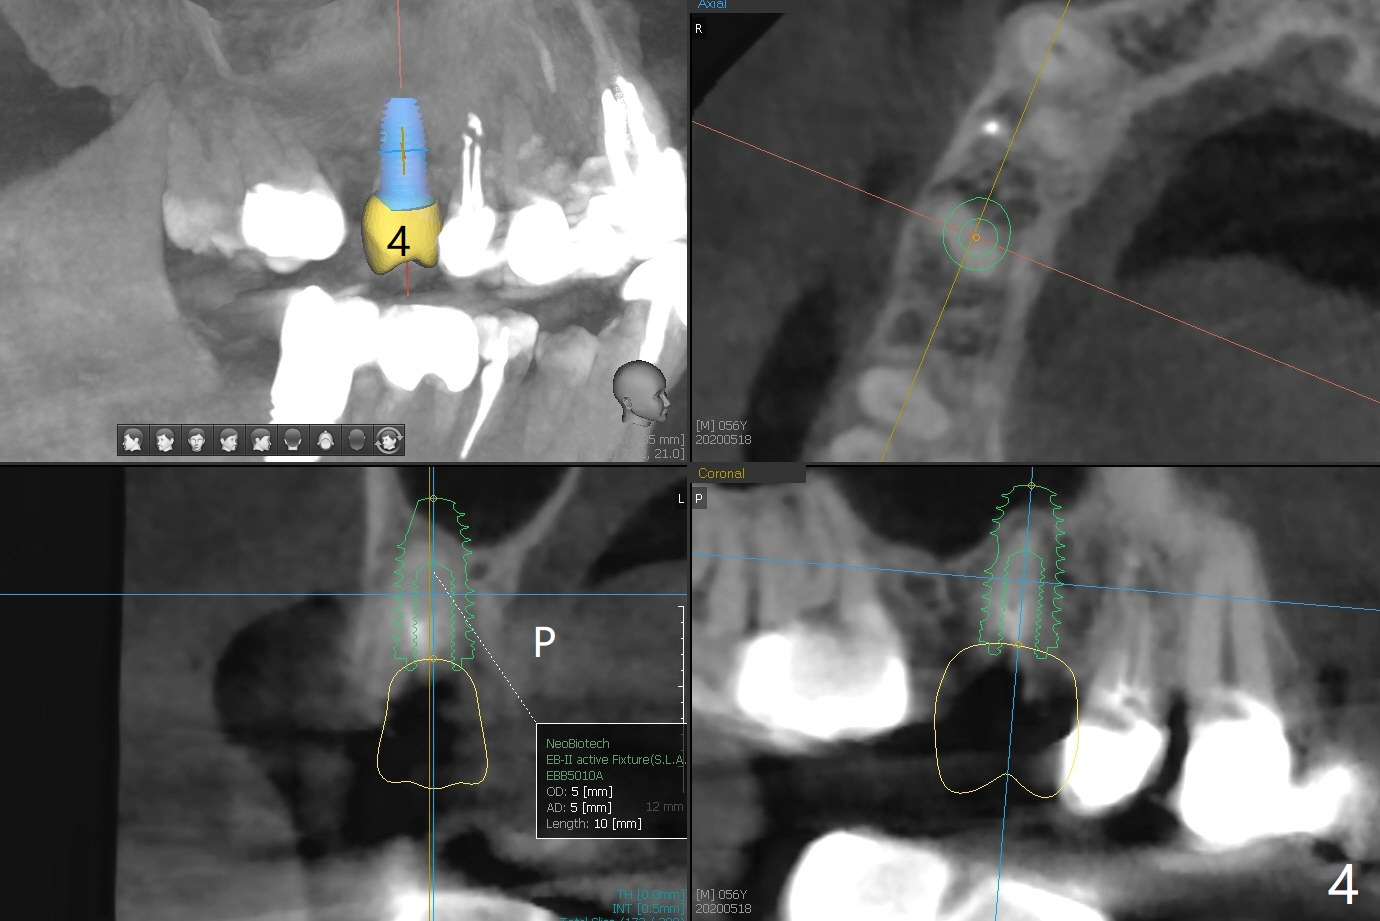

A 56-year-old man complains of food impaction under UR FPD (fixed partial denture, bridge). Floss goes through between #4 abutment and retainer (Fig.1 red arrow and *). After sectioning the FPD as indicated by black dashed line in Fig.2,3, try to initiate osteotomy at #3 with 1.2 and 1.5 mm drills for 5 mm (bone height) and 1.0 and 1.5 mm Tatum micro-osteotomes for sinus lift and place a 2x8.5 mm IS mini-implant. If it is feasible, place a 4x14 mm tissue-level implant slightly mesial at #4 (Fig.5). If not, place a larger one (5.0 mm) slightly distal for a cantilever FPD (Fig.4).